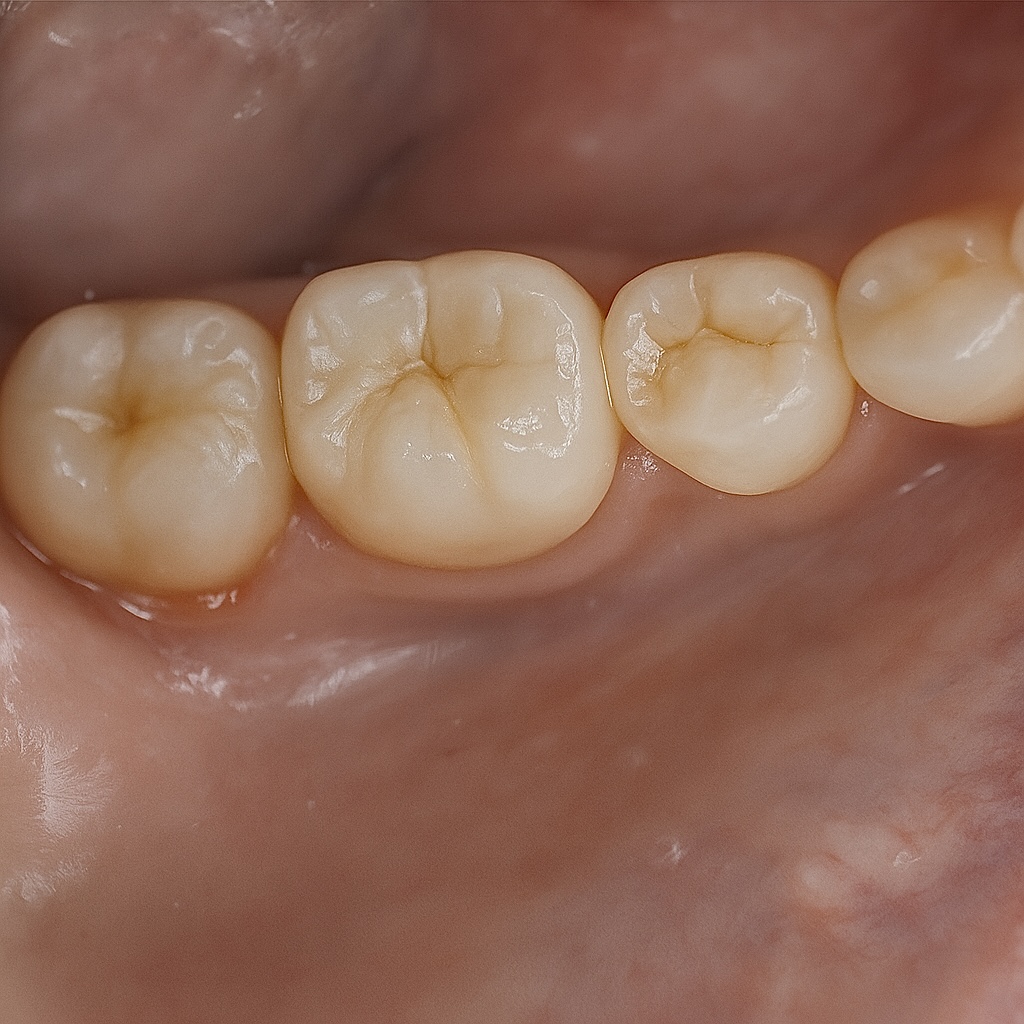

A full-coverage zirconia crown was fabricated to mimic occlusal morphology (Fig 4). Try-in confirmed marginal adaptation and occlusal contacts. Final bonding performed with Panavia V5 resin cement under isolation.

Radiograph confirmed ideal obturation, core adaptation, and marginal integrity (Fig 3). The final restoration blended esthetically and functionally with the dentition (Fig 5).

- Fig 4: Monolithic zirconia crowns ready for cementation.

- Fig 5: Final clinical result demonstrating functional and esthetic integration.